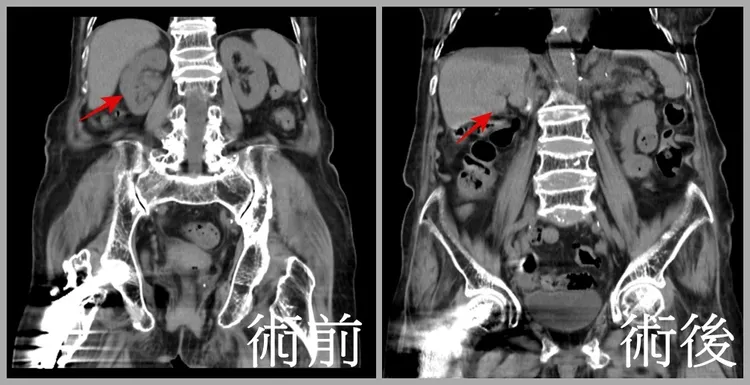

經安排電腦斷層和核磁共振檢查後,果然發現阿嬤右側腎盂有腫瘤,且已侵犯到腎盂旁的脂肪,確診為第三期腎盂及輸尿管癌,幸好並未轉移到其他器官,因此醫療團隊建議盡快手術切除為宜。

術後阿嬤也快速拔管,無需轉入加護病房觀察,並在孫女的細心照顧下,住院10天後即順利出院,之後孫女每次都陪著阿嬤回診,扮演最強後盾,也帶著阿嬤遊山玩水,追蹤2年來,無論是電腦斷層、磁振造影和膀胱鏡檢查均顯示腫瘤無任何復發跡象,可說是抗癌成功,阿嬤每天也在家人陪伴下,靜謐地享受天倫之樂。

患者接受達文西手術治療並追蹤2年後,癌細胞都沒有擴散跡象,可說是成功抗癌。亞大醫院提供